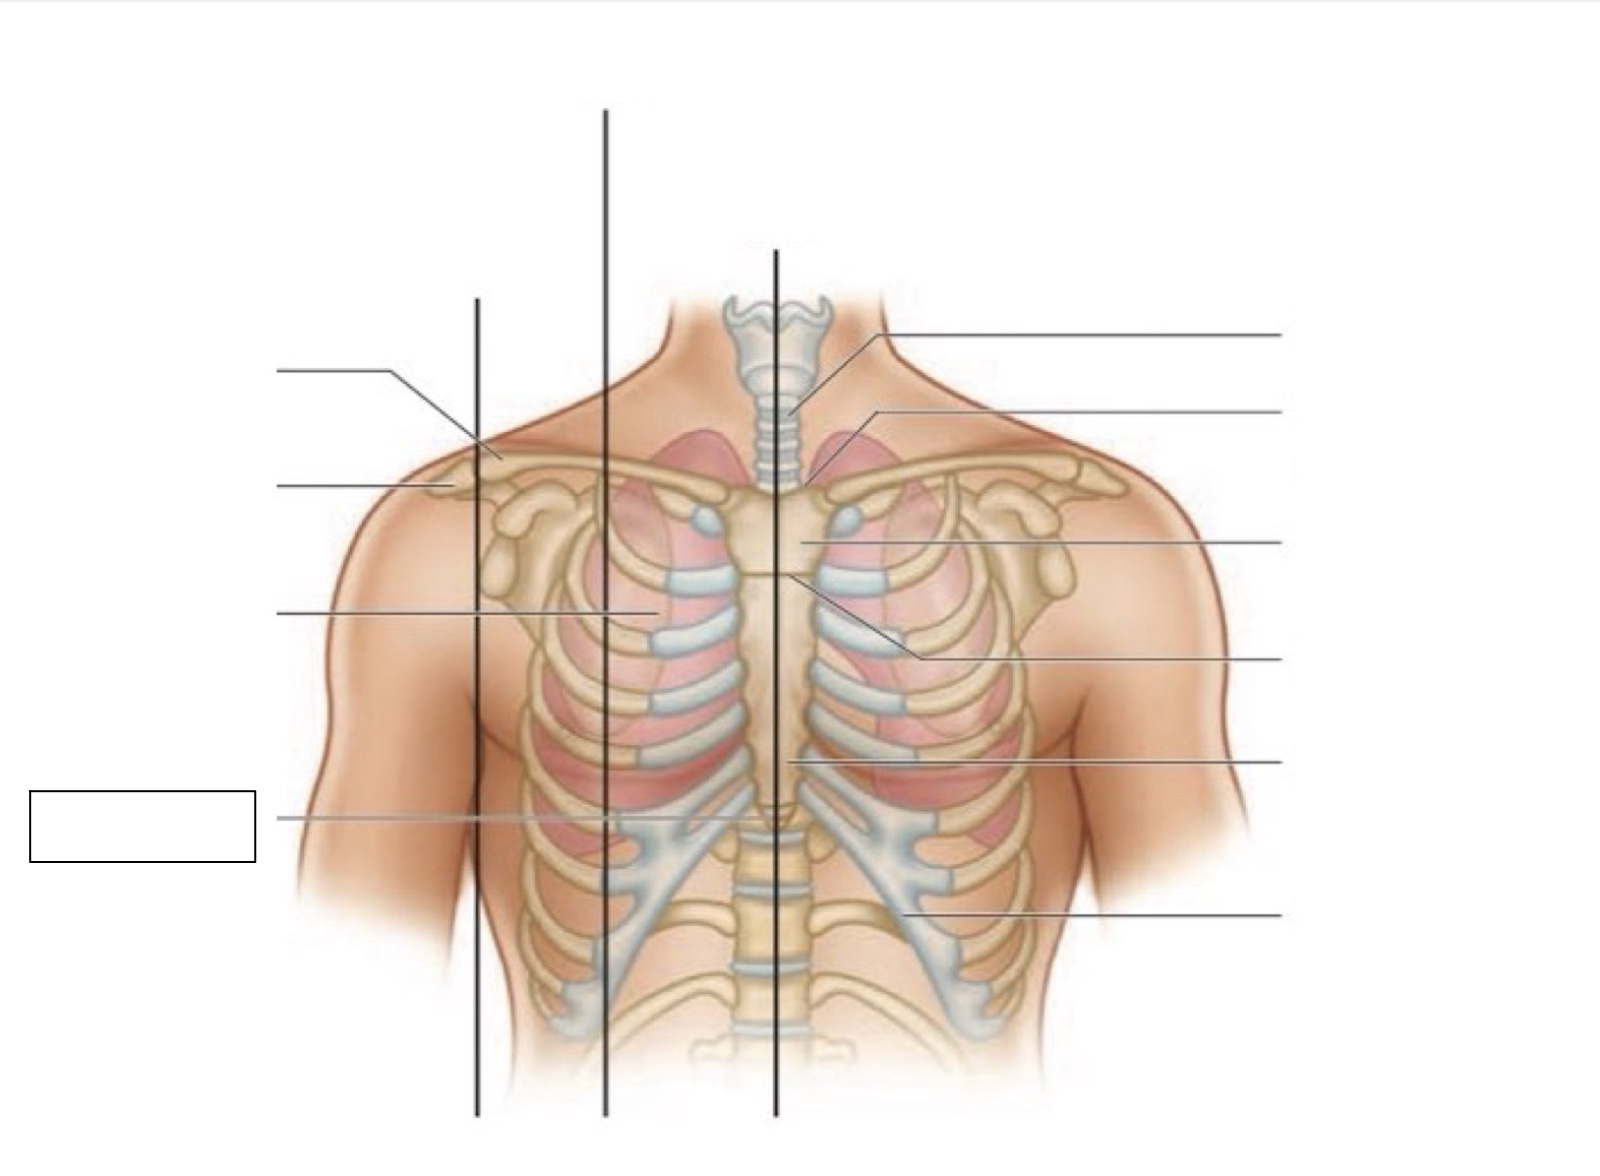

inferior angle of scapula

scapula

midscapular line

midspinal line

spinous process

thoracic cavity

diaphragm